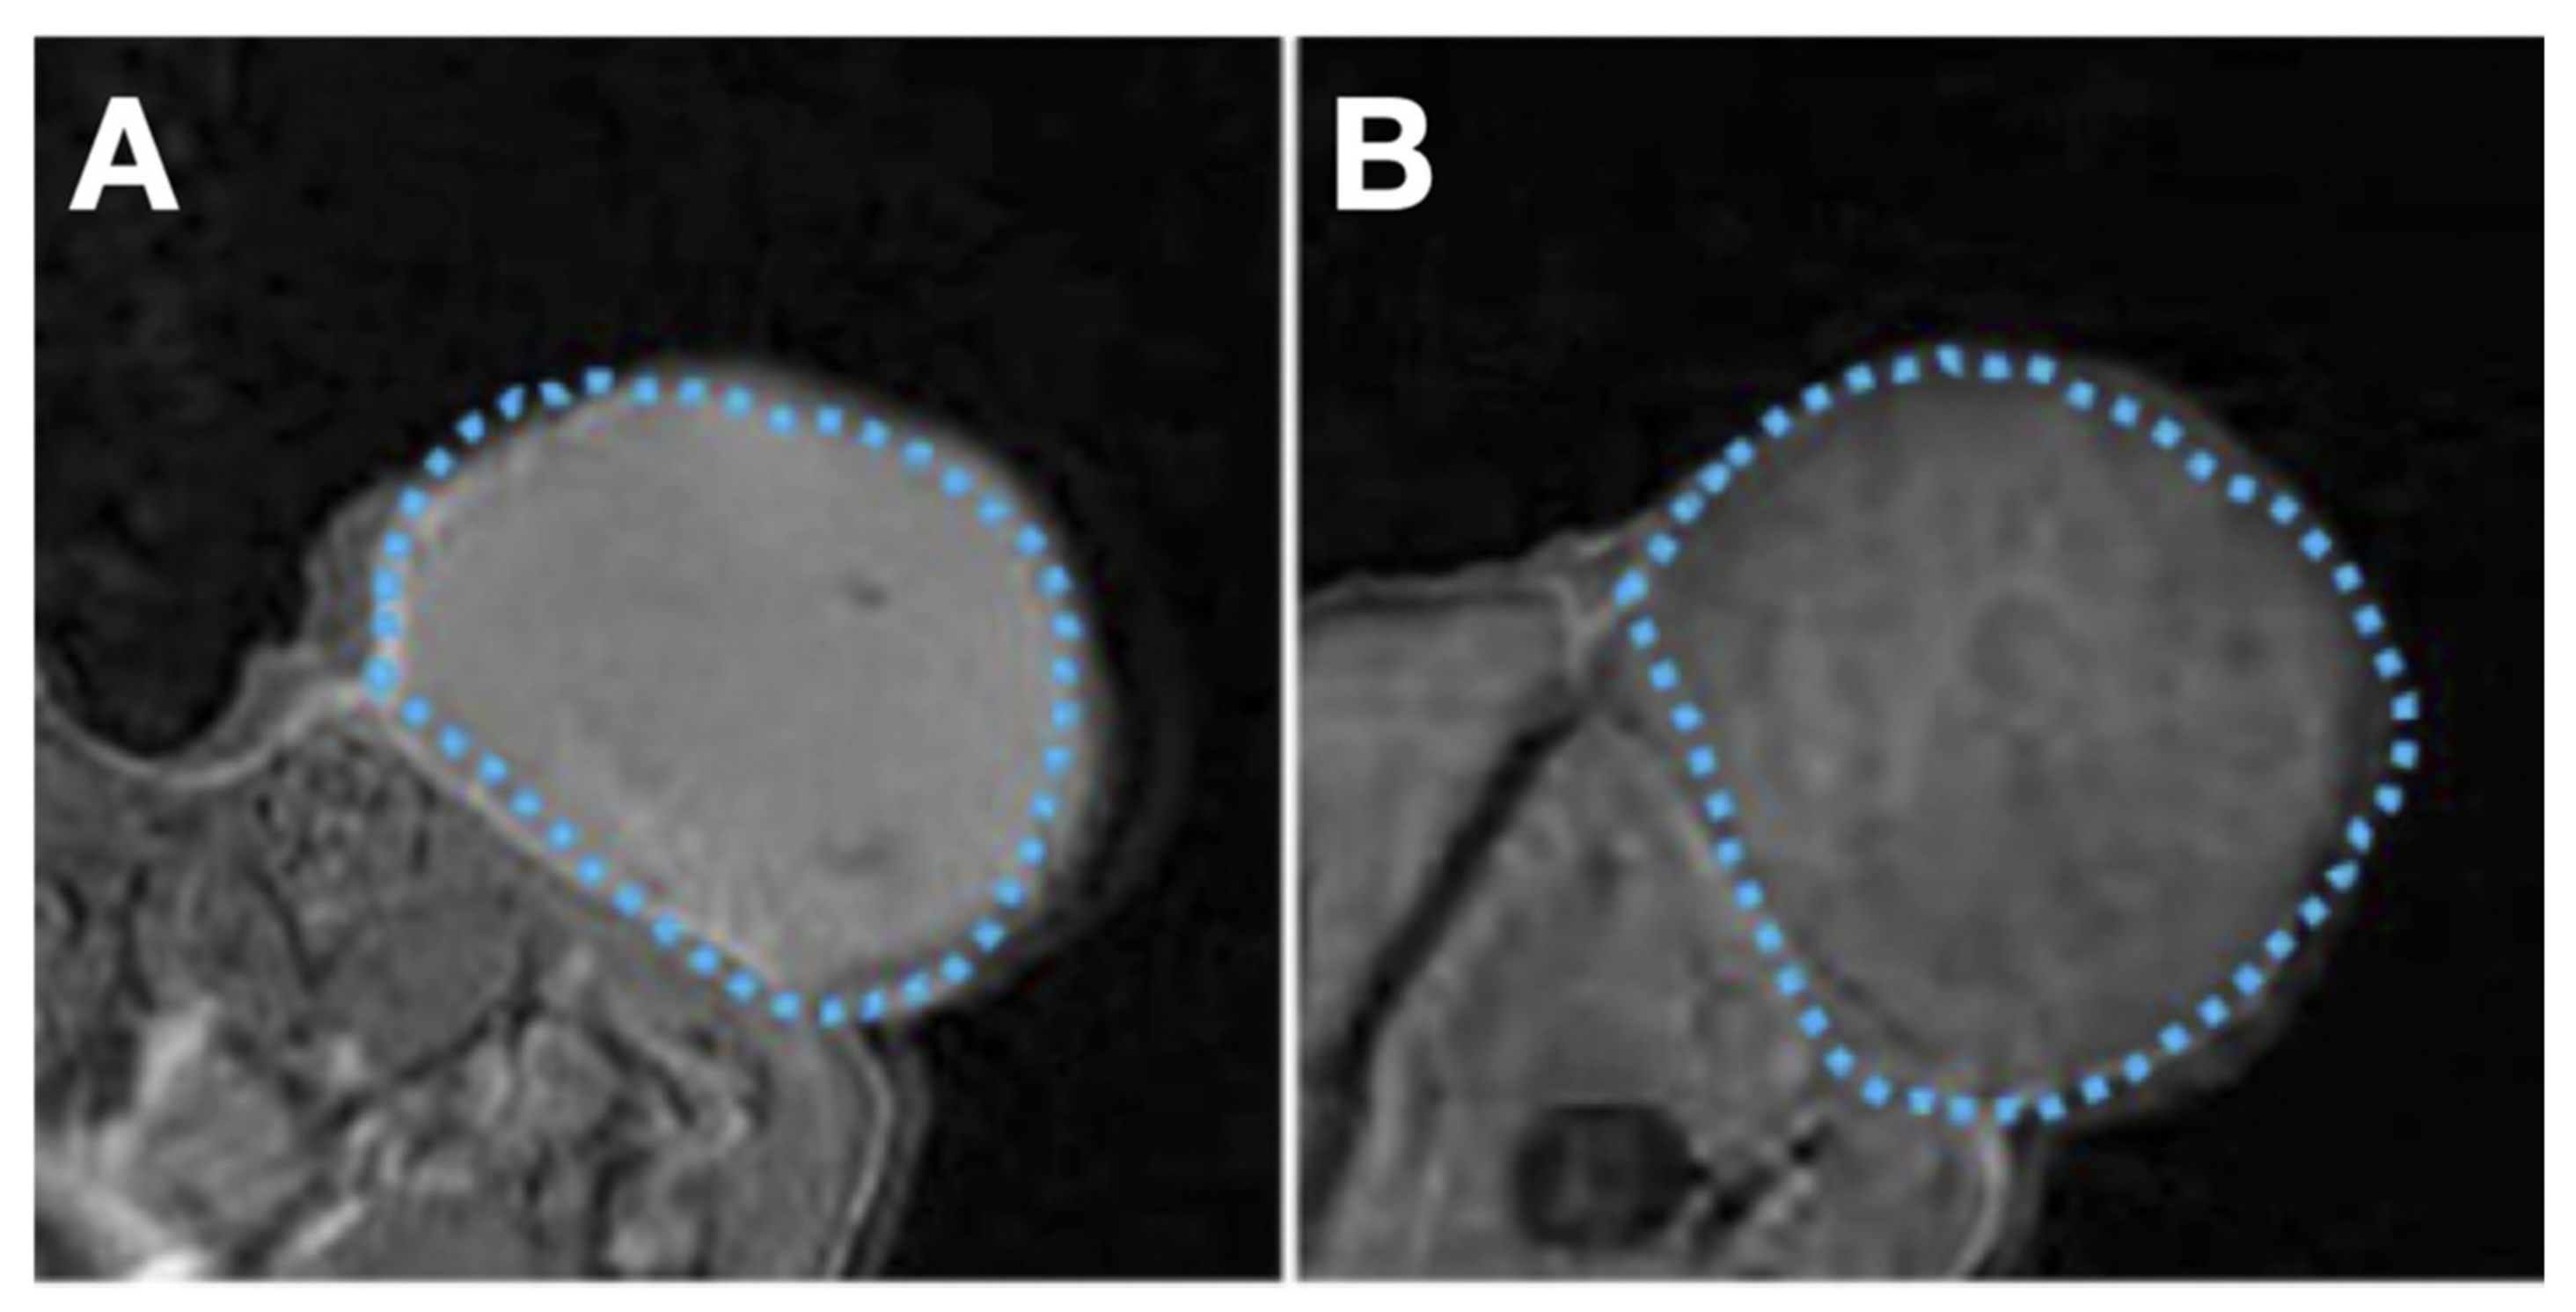

- Rose, F.D.; Braeuer, M.; Braesch-Andersen, S.; Otto, A.M.; Steiger, K.; Reder, S.; Mall, S.; Nekolla, S.; Schwaiger, M.; Weber, W.A.; et al. Galectin-3 Targeting in Thyroid Orthotopic Tumors Opens New Ways to Characterize Thyroid Cancer. J. Nucl. Med. 2019, 60, 770–776. [Google Scholar] [CrossRef]

- Peplau, E.; Rose, F.D.; Reder, S.; Mittelhäuser, M.; Scafetta, G.; Schwaiger, M.; Weber, W.A.; Bartolazzi, A.; Skerra, A.; D’Alessandria, C. Development of a Chimeric Antigen-Binding Fragment Directed Against Human Galectin-3 and Validation as an Immuno-Positron Emission Tomography Tracer for the Sensitive In Vivo Imaging of Thyroid Cancer. Thyroid 2020, 30, 1314–1326. [Google Scholar] [CrossRef]

- Peplau, E.; Rose, F.D.; Eichinger, A.; Reder, S.; Mittelhäuser, M.; Scafetta, G.; Schwaiger, M.; Weber, W.A.; Bartolazzi, A.; D’Alessandria, C.; et al. Effective Rational Humanization of a PASylated Anti-Galectin-3 Fab for the Sensitive PET Imaging of Thyroid Cancer in Vivo. Sci. Rep. 2021, 11, 7358. [Google Scholar] [CrossRef]